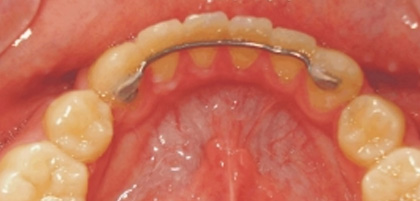

3. 下顎弓犬齒到犬齒舌側固定線

犬齒到犬齒舌側固定線是個簡單舒適的固定式維護器,常使用於下顎弓。

下顎弓犬齒到犬齒舌側固定線